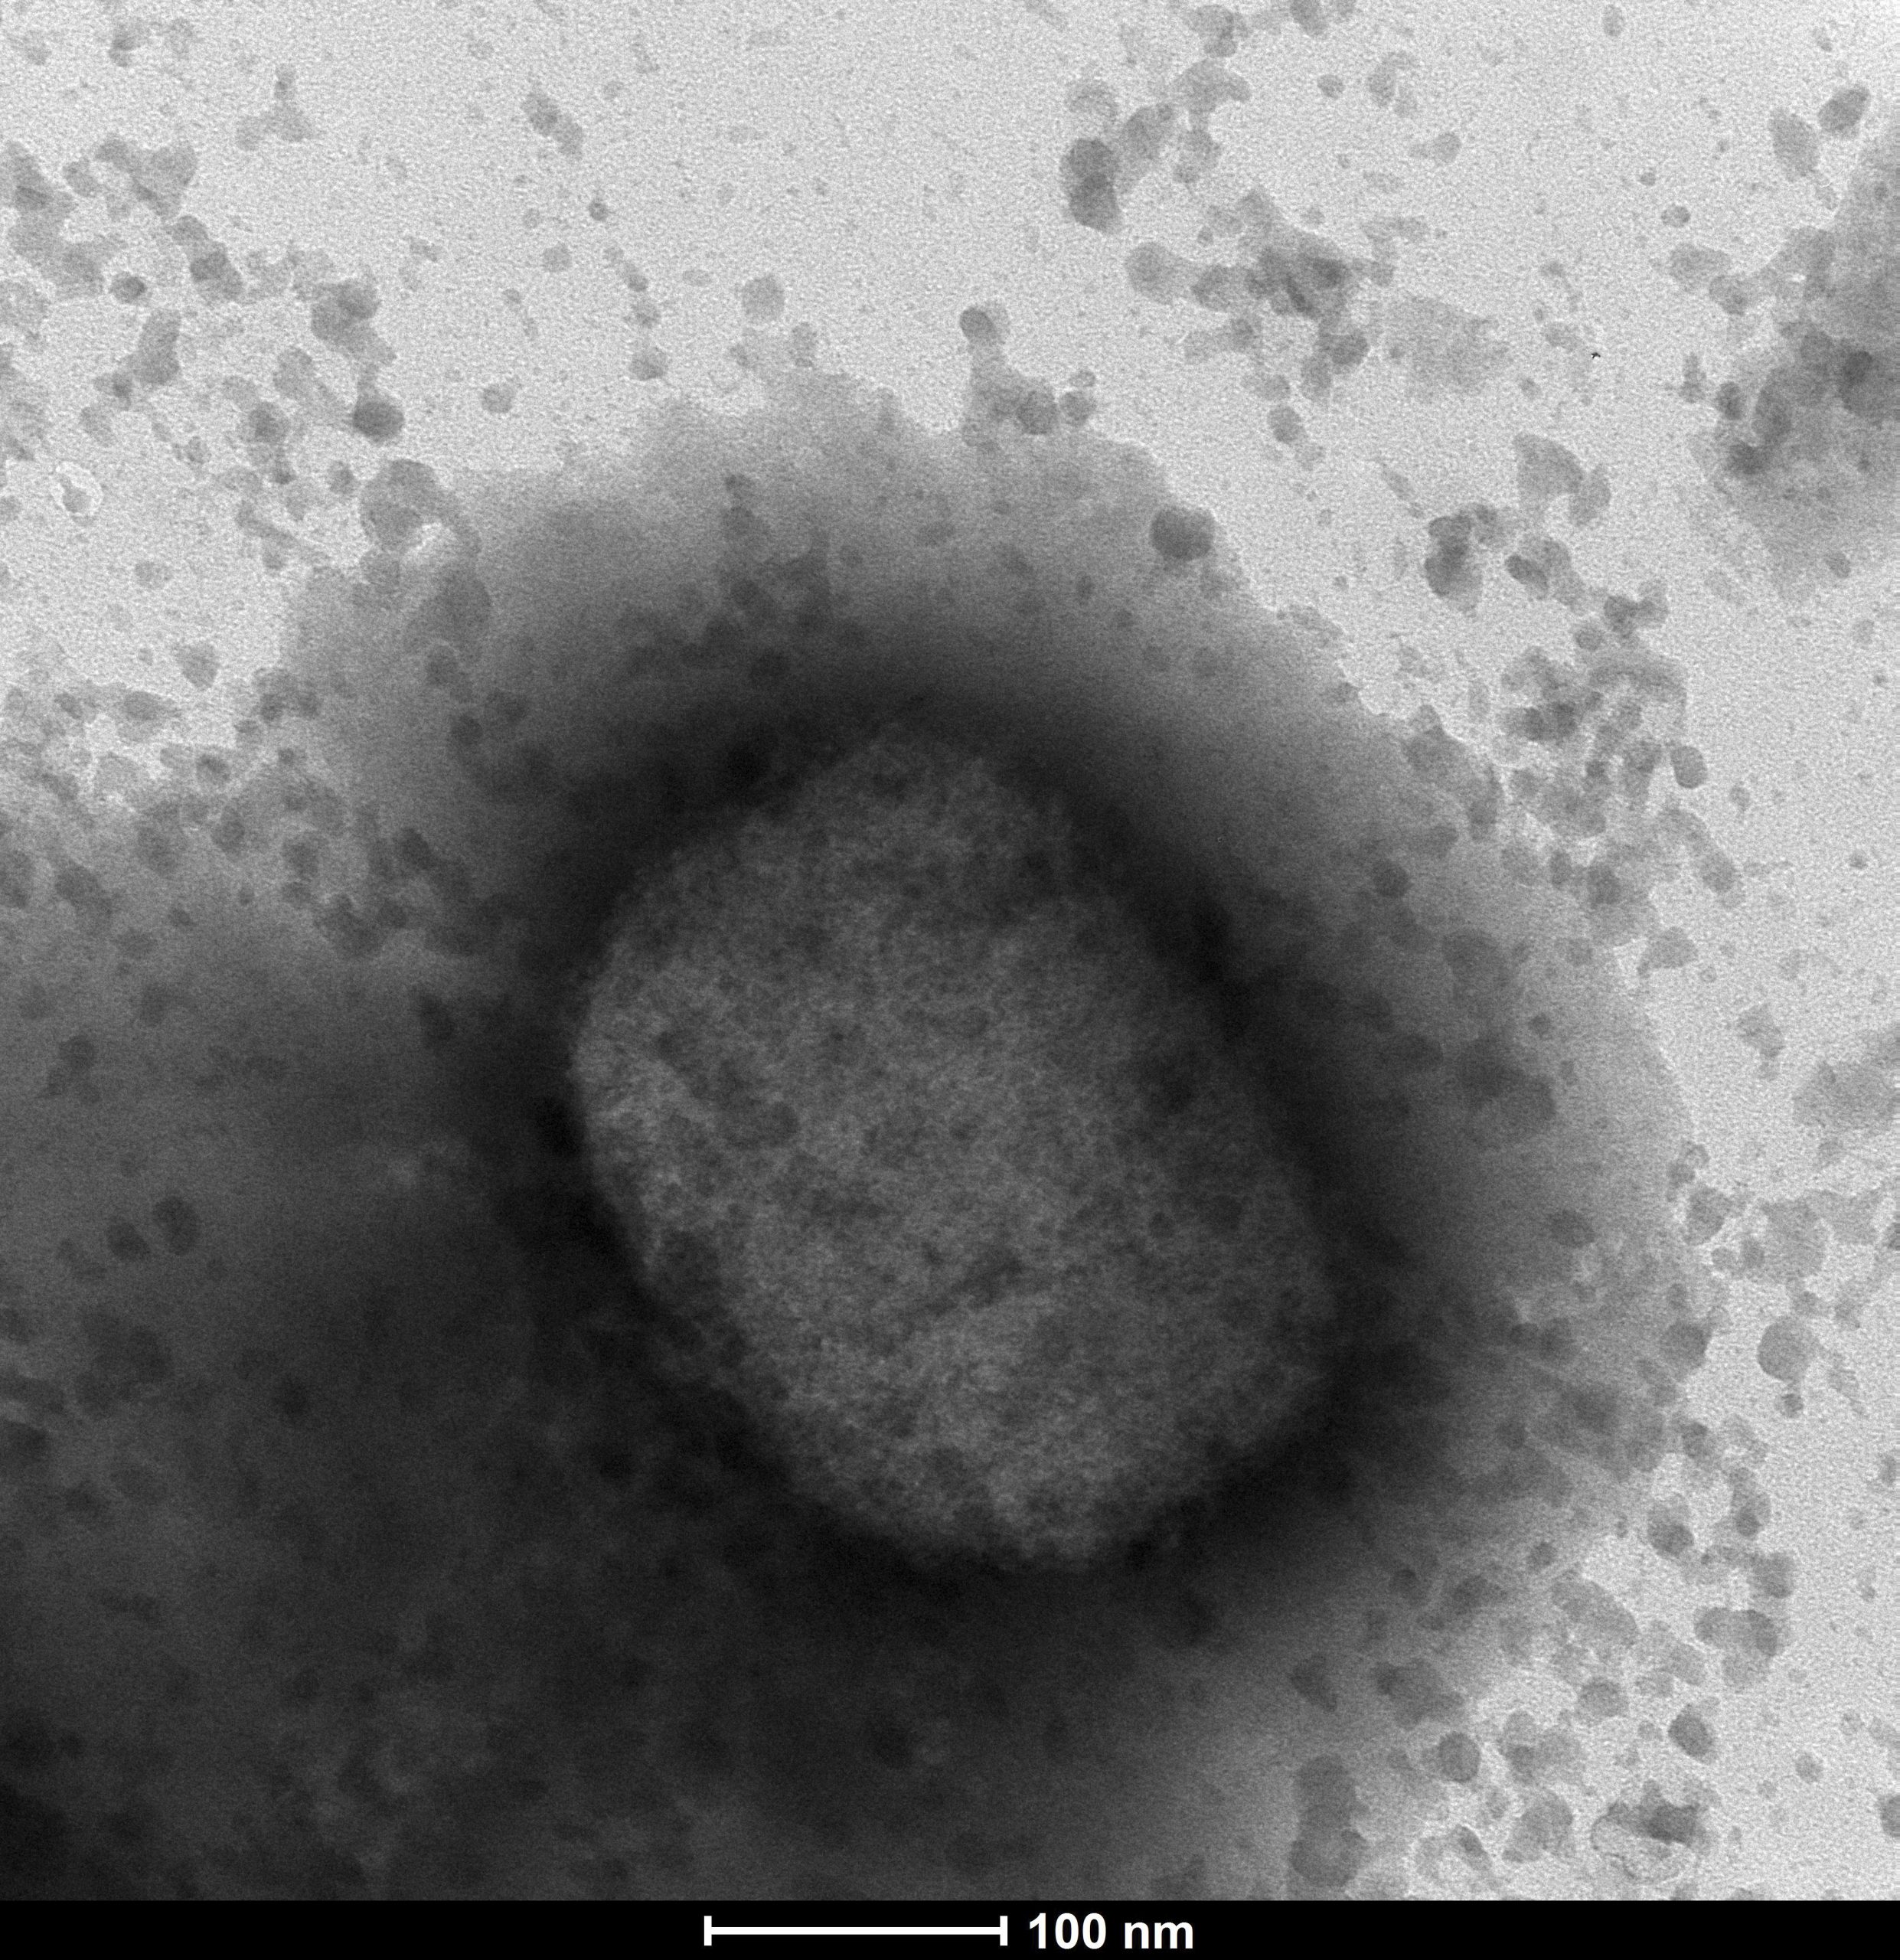

欧盟致力于集中采购猴痘疫苗

(布鲁塞尔27日综合电)欧盟(EU)周四告诉法新电,正通过欧盟卫生紧急情况和准备 权威机构(HERA)致力于集中购买猴痘疫苗和治疗药物,并将在“未来数天内”商定细节。

欧盟疾病机构表示,猴痘的病例目前在全球已累积219例。前欧盟成员国英国有71例,欧盟国家西班牙有84例,葡萄牙有37例。美国疾病控制与预防中心 (CDC) 周四表示,美国在7个州里确认了9例猴痘病例。